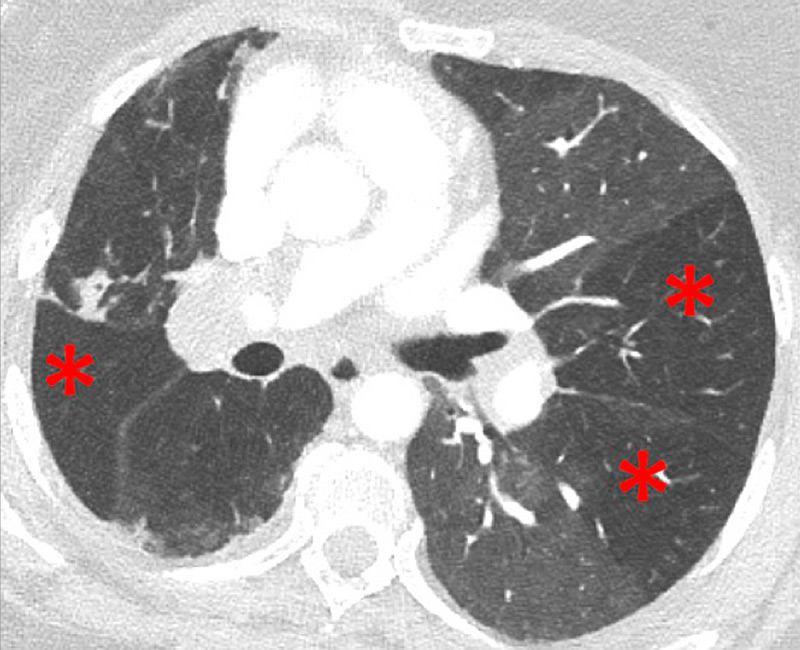

Figure 2

Chronic thromboembolic pulmonary hypertension (CTEPH). Vascular (A) and parenchymal (B) signs of CTEPH with proximal marginal occlusion (arrows) and mosaic pattern (stars). Functional information simply added with triangular perfusion defects (stars) on the iodine maps (C).